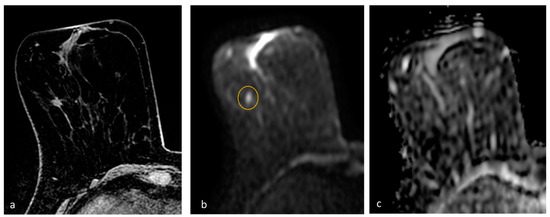

- Amornsiripanitch, N.; Bickelhaupt, S.; Shin, H.J.; Dang, M.; Rahbar, H.; Pinker, K.; Partridge, S.C. Diffusion-weighted MRI for Unenhanced Breast Cancer Screening. Radiology 2019, 293, 504–520. [Google Scholar] [CrossRef]

- Trimboli, R.M.; Verardi, N.; Cartia, F.; Carbonaro, L.A.; Sardanelli, F. Breast cancer detection using double reading of unenhanced MRI including T1-weighted, T2-weighted STIR, and diffusion-weighted imaging: A proof of concept study. AJR Am. J. Roentgenol. 2014, 203, 674–681. [Google Scholar] [CrossRef]

- Baltzer, P.A.; Benndorf, M.; Dietzel, M.; Gajda, M.; Camara, O.; Kaiser, W.A. Sensitivity and specificity of unenhanced MR mammography (DWI combined with T2-weighted TSE imaging, ueMRM) for the differentiation of mass lesions. Eur. Radiol. 2010, 20, 1101–1110. [Google Scholar] [CrossRef] [PubMed]

- Baltzer, P.A.T.; Bickel, H.; Spick, C.; Wengert, G.; Woitek, R.; Kapetas, P.; Clauser, P.; Helbich, T.H.; Pinker, K. Potential of Noncontrast Magnetic Resonance Imaging with Diffusion-Weighted Imaging in Characterization of Breast Lesions: Intraindividual Comparison with Dynamic Contrast-Enhanced Magnetic Resonance Imaging. Investig. Radiol. 2018, 53, 229–235. [Google Scholar] [CrossRef]

- Yamada, T.; Kanemaki, Y.; Okamoto, S.; Nakajima, Y. Comparison of detectability of breast cancer by abbreviated breast MRI based on diffusion-weighted images and postcontrast MRI. Jpn. J. Radiol. 2018, 36, 331–339. [Google Scholar] [CrossRef]

- Bickelhaupt, S.; Tesdorff, J.; Laun, F.B.; Kuder, T.A.; Lederer, W.; Teiner, S.; Maier-Hein, K.; Daniel, H.; Stieber, A.; Delorme, S.; et al. Independent value of image fusion in unenhanced breast MRI using diffusion-weighted and morphological T2-weighted images for lesion characterization in patients with recently detected BI-RADS 4/5 X-ray mammography findings. Eur. Radiol. 2017, 27, 562–569. [Google Scholar] [CrossRef]